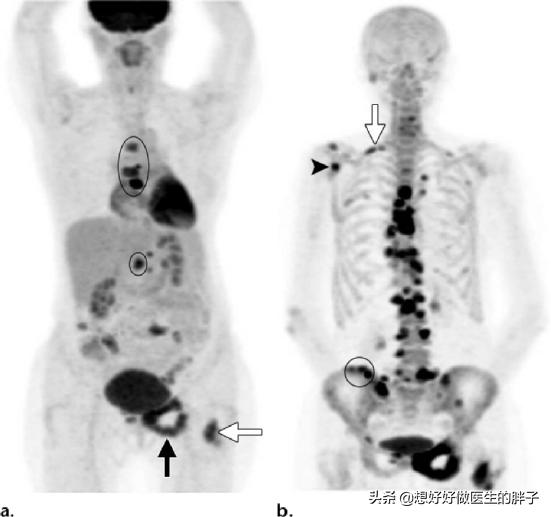

Quel type de douleur doit alerter sur la présence de métastases osseuses ? Les métastases osseuses sont une manifestation fréquente des tumeurs malignes à un stade avancé. La tumeur primaire présente dans d'autres parties du corps se métastase dans les os par les voies sanguines et lymphatiques, formant ainsi des métastases osseuses. Les métastases osseuses signifient que le tissu osseux normal a été détruit et remplacé par du tissu tumoral. Les métastases osseuses peuvent être classées en trois types selon la spécificité de la lésion : le type ostéolytique, le type ostéogénique et le type mixte. Les sites courants de métastases osseuses sont l'os de la diaphyse moyenne (colonne vertébrale et bassin), les côtes et la métaphyse inférieure, l'os de la diaphyse moyenne étant le plus courant, ce qui est lié aux caractéristiques de l'apport sanguin dans cette zone. Comme le montre le cercle ci-dessous, les métastases osseuses sont multiples et la colonne vertébrale est en mauvais état.

Pour les patients sans antécédents de cancer, et si la famille est financièrement aisée, il est recommandé de réaliser un examen PET-CT pour rechercher des lésions cancéreuses suspectes sur l'ensemble du corps, ce qui permet de déterminer de manière adéquate la présence de lésions tumorales, leur degré d'évolution et le type de foyers métastatiques qu'elles présentent.

En cas d'antécédents de cancer et si le degré de malignité est jugé élevé à l'époque, il est possible de déterminer la présence de métastases osseuses par une scintigraphie osseuse du corps entier. Parallèlement, le degré de destruction osseuse au niveau du site de la métastase peut être clarifié par un examen par résonance magnétique.